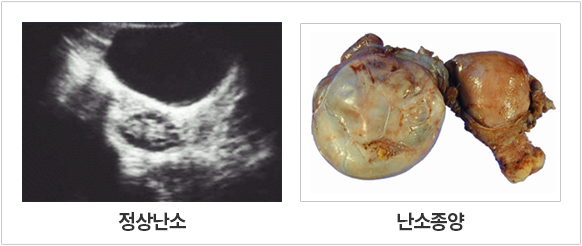

³­¼ÒÁ¾¾çÀ̶õ?

¸ðµç ºÎÀÎ¾Ï Áß¿¡¼­ ³­¼ÒÀÇ ¾Ç¼ºÁ¾¾çÀÌ ÀÓ»óÀûÀ¸·Î Á¦ÀÏ Á߿伺À» ¶ì¸ç ¿©¼º°Ç°­¿¡ Å« ¿µÇâÀ» ¹ÌÄ£´Ù°í ÇØµµ °ú¾ðÀÌ ¾Æ´Õ´Ï´Ù. ´ëºÎºÐÀÇ ³­¼Ò¾Ï ȯÀÚÀÇ 2/3À̻󿡼­ ¾ÏÀÌ ÁøÇàµÈ »óÅ¿¡¼­ ¹ß°ßÀÌ µË´Ï´Ù. ³­¼Ò¾ÏÀÇ ¹ßº´¿¬·ÉÀº ´ëºÎºÐ(80%ÀÌ»ó) Æó°æÈÄÀÇ ¿©¼º¿¡¼­ ¹ßº´ÇÏ¸ç ³­¼Ò¾ÏÀÇ Á¶±â¹ß°ßÀ» À§ÇØ Áú½Ä ÃÊÀ½ÆÄ¿Í CA-125Ç÷¾×°Ë»ç ¹× Á¤±âÀû ³»ÁøÀÌ Á¦½ÃµÇ°í ÀÖÀ¸³ª ¾ÆÁ÷ ±× È¿¿ë¼ºÀÌ ¿ÏÀüÈ÷ ÀÔÁõµÇÁö´Â ¾Ê°í ÇöÀç ¿¬±¸°¡ ÁøÇàÁß À̶ó°í ÇÕ´Ï´Ù. ³­¼Ò¾ÏÀÇ Ä¡·á´Â ´ëºÎºÐ ¼ö¼ú°ú È­ÇÐÄ¡·á·Î ´ëº¯µË´Ï´Ù. ³­¼Ò¾ÏÀÇ »ýÁ¸À²Àº ±×·¯³ª Ÿ ºÎÀξϿ¡ ºñÇØ ¸¹ÀÌ ¶³¾îÁö´Â °ÍÀÌ »ç½ÇÀÔ´Ï´Ù.